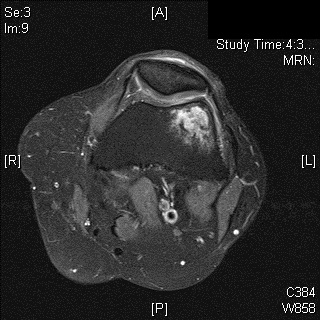

MRI

• MR Imaging, demonstrates intermediate to hypointense signal on T1-weighted images (Fig. 4 & 5) and hyperintensity on T2-weighted images (Fig. 6 & 7).

Fig. 6

Fig. 7

Fig. 6 & 7: MR Imaging. Axial (Fig. 6) and Coronal (Fig. 7) T2 fat saturated image demonstrating T2 hyperintense lesion within the lateral supracondylar femur with a small amount of surrounding bone marrow edema.